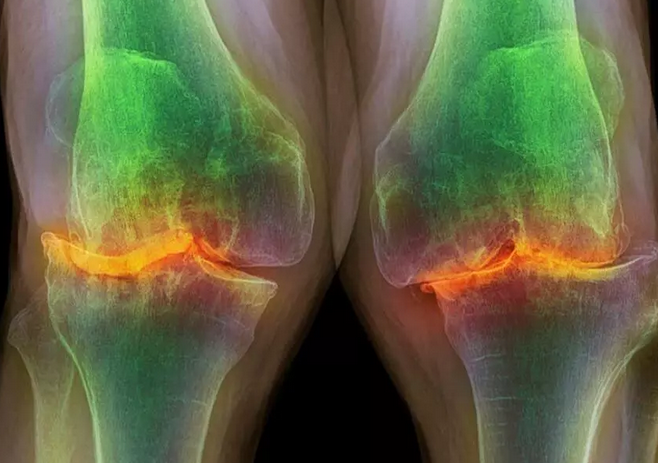

ایرج عبداللهی رئیس انجمن فیزیوتراپی ایران در گفتگو با خبرنگار سلامت خبرگزاری علم و فناوری آنا، اظهار کرد: آرتروز یکی از شایعترین مشکلات اسکلتی عضلانی است که در مفاصل مختلف رخ میدهد.

وی ادامه داد: آرتروز بیشتر در زانو و ستون فقرات دیده میشود به طوری که آرتروز زانو و کمر شایعتر از مفاصل دیگر است. معمولا با افزایش سن، در اثر فشارهایی که در طور زندگی به غضروف مفصلی وارد میشود ضخامت این غضروف کمتر میشود که در اصطلاح به این کم شدن ضخامت غضروف مفصلی آرتروز میگویند.